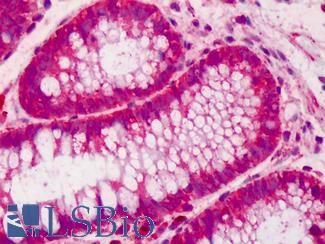

Anti-Villin antibody IHC of human small intestine, epithelial membrane. Immunohistochemistry of formalin-fixed, paraffin-embedded tissue after heat-induced antigen retrieval. Antibody LS-B8547 dilution 10 ug/ml.

Villin